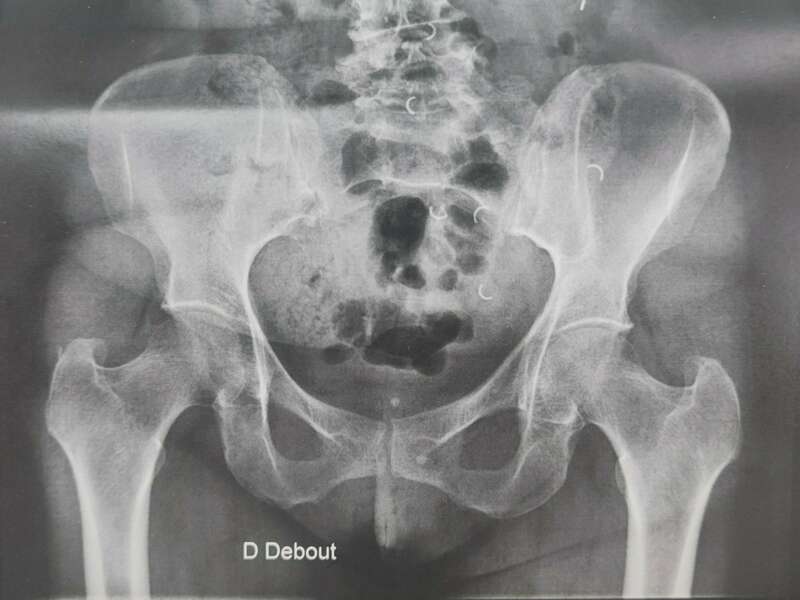

L’articulation de la hanche appelée aussi articulation coxo-fémorale met en relation la cavité articulaire du bassin (Cotyle) et la tête fémorale. Ces deux structures sont fermement emboîtées et sont entourées d’une capsule articulaire, de puissants ligaments et d’une chape musculaire. La mobilité de la tête fémorale dans le cotyle est facilité par le cartilage qui recouvre les deux surfaces osseuses et par le liquide articulaire ou synovial qui améliore le mouvement et nourrit le cartilage.

L’arthrose désigne un processus d’usure du cartilage liée au vieillissement. Ce n’est pas une fatalité liée à l’âge. Elle cause des dommages irréversible du cartilage qui perd au fur et à mesure son rôle de surface de glissement et d’amortisseur. La pression sur l’os s’accroît à mesure que l’épaisseur cartilagineuse diminue. Des excroissances osseuses, appelées ostéophytes, des kystes osseux et des ulcérations cartilagineuses se forment progressivement.

L’arthrose n’entraine pas toujours des douleurs. On parle de dissociation radio-clinique : une arthrose visible radiologiquement n’est pas forcément responsable de douleurs. Dans ce cas, aucun traitement n’est nécessaire.

Elle sera confirmée par des examens radiologiques tels que des radiographies de hanche. En cas de doute diagnostic, afin d’éliminer un éventuel diagnostic différentiel, un scanner et/ou une IRM pourront être prescrits.